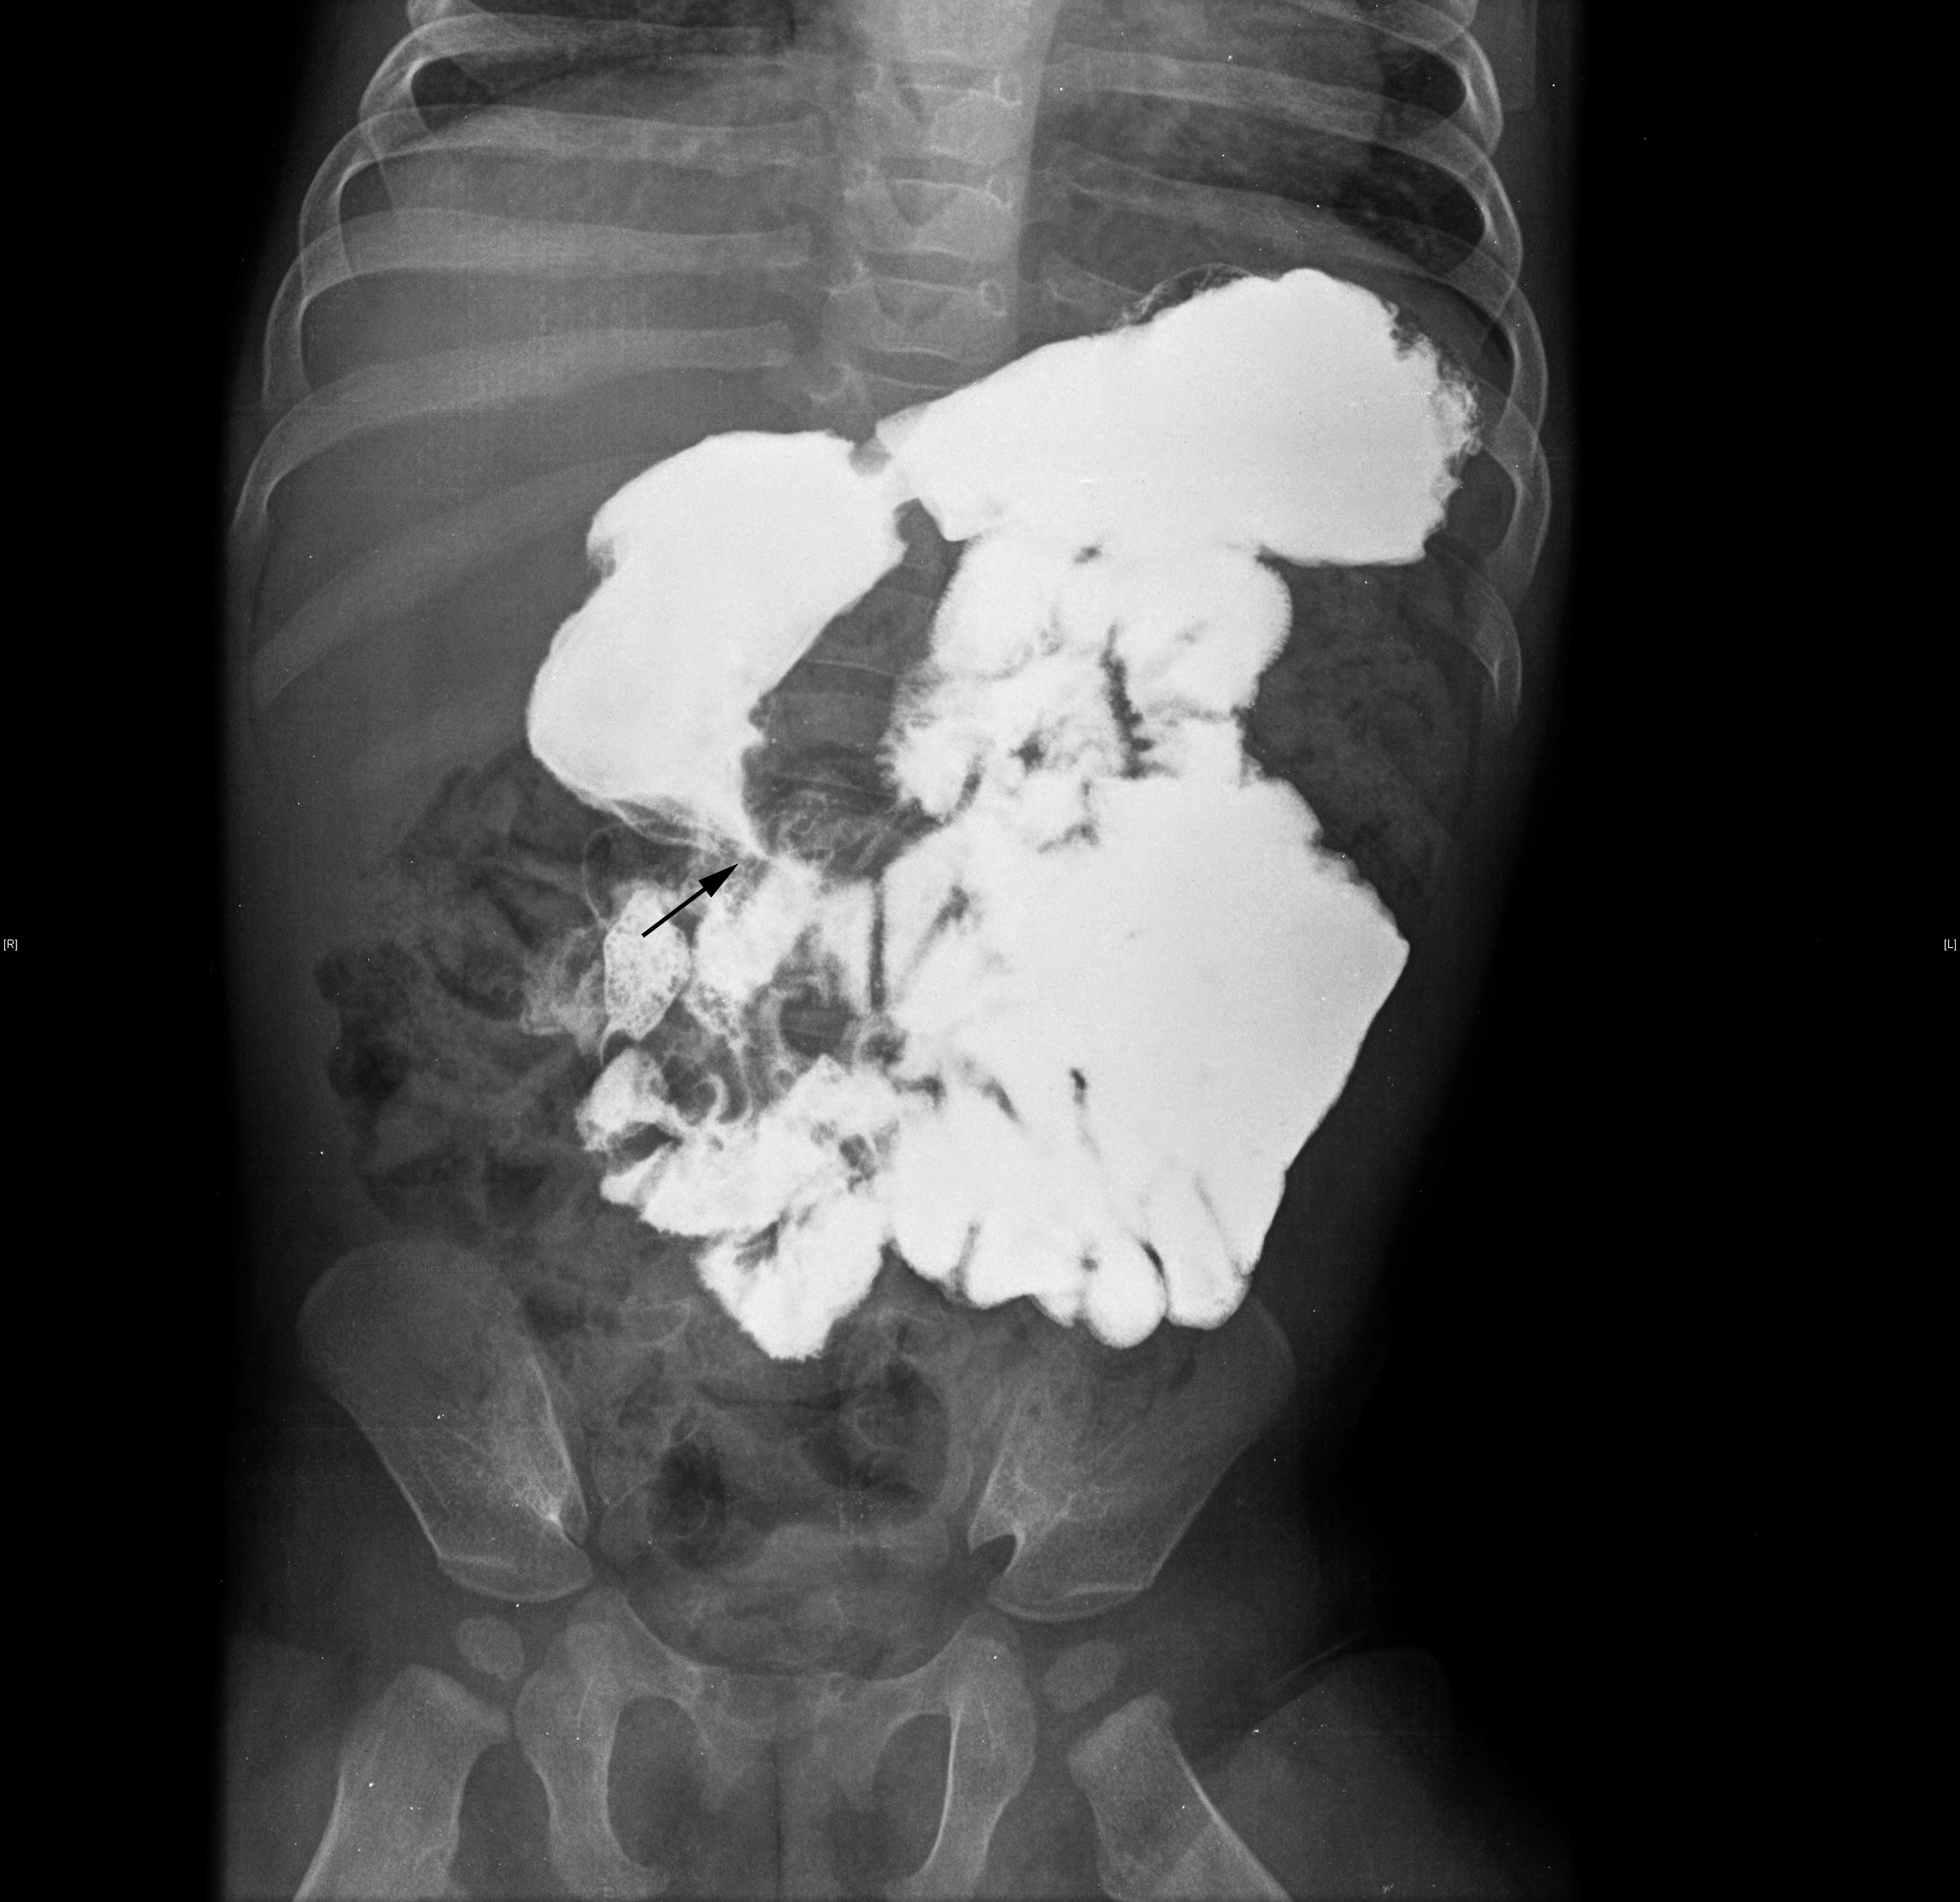

A obstrução duodenal congénita, secundária a atresia ou estenose, tem tipicamente apresentação no período neonatal com sinais de oclusão intestinal alta. Todavia, uma apresentação mais tardia e diversa pode ocorrer nos raros casos de obstrução parcial do duodeno devido à presença de uma membrana duodenal perfurada, colocando sérios desafios no seu diagnóstico.Reportam-se três casos clínicos de obstrução duodenal congénita com apresentação após o período neonatal. Os três casos partilham uma história de vómitos recorrentes e má progressão ponderal com início após a diversificação alimentar. A identificação de achados radiológicos específicos, tais como os sinais de dupla bolha e de wind sock, foi determinante para o diagnóstico.A obstrução duodenal congénita devido à presença de uma membrana duodenal perfurada é uma entidade rara e o seu reconhecimento nem sempre imediato. Uma história clínica minuciosa, aliada a achados radiológicos específicos, constitui a chave para um diagnóstico atempado dos casos de obstrução duodenal congénita com apresentação tardia.